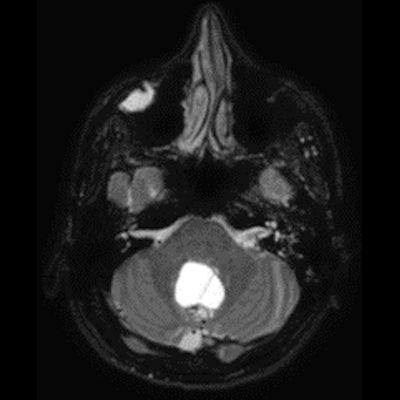

24 yaş, E

Baş ağrısı

4.ventrikül tabanına oturmuş posterior fossada hemanjioblastoma

bilateral vestibuler schwannoma ve kist duvarı kontrastlanmaması nedeniyle hemangioblastom ancak yeri itibariyle pilositik astrositom ayırıcı tanısı

Hemangioblastoma